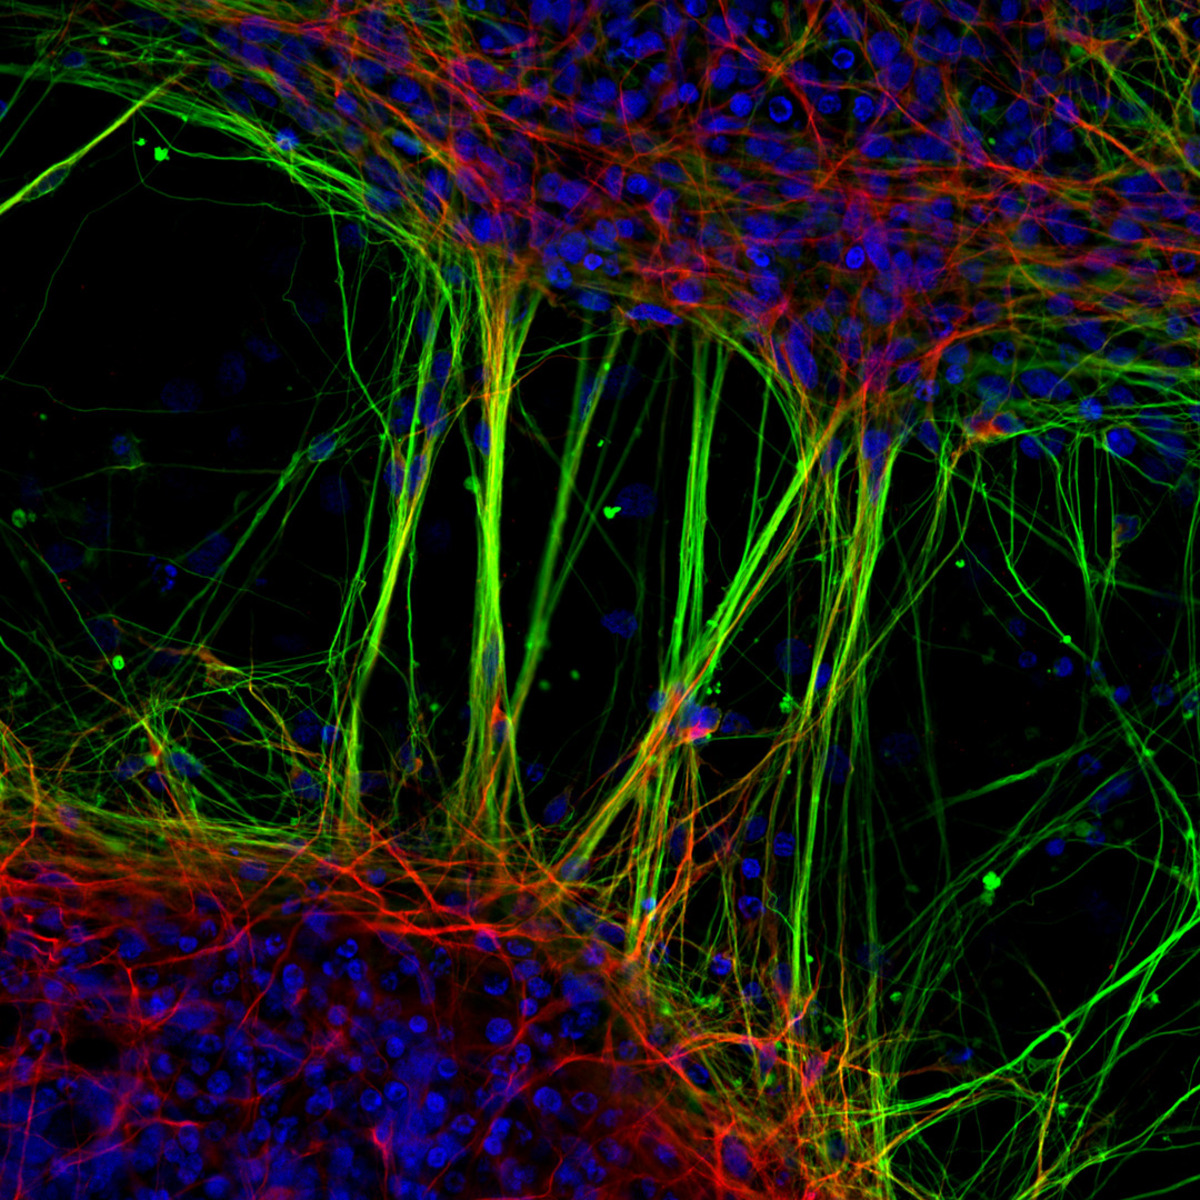

2. Νευρώνες

Ο Δρ. Jianqun Gao και η καθηγήτρια Glenda Halliday καταγράφουν καταπληκτικά ανθρώπινους νευρώνες που προέρχονται από νευρικά βλαστοκύτταρα. Η φωτογραφία απέσπασε την 7η θέση στον διαγωνισμό.